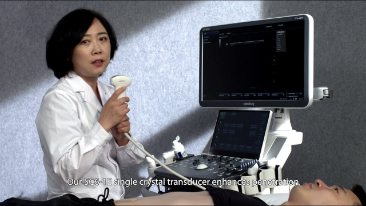

Immagini cliniche

Trasduttori